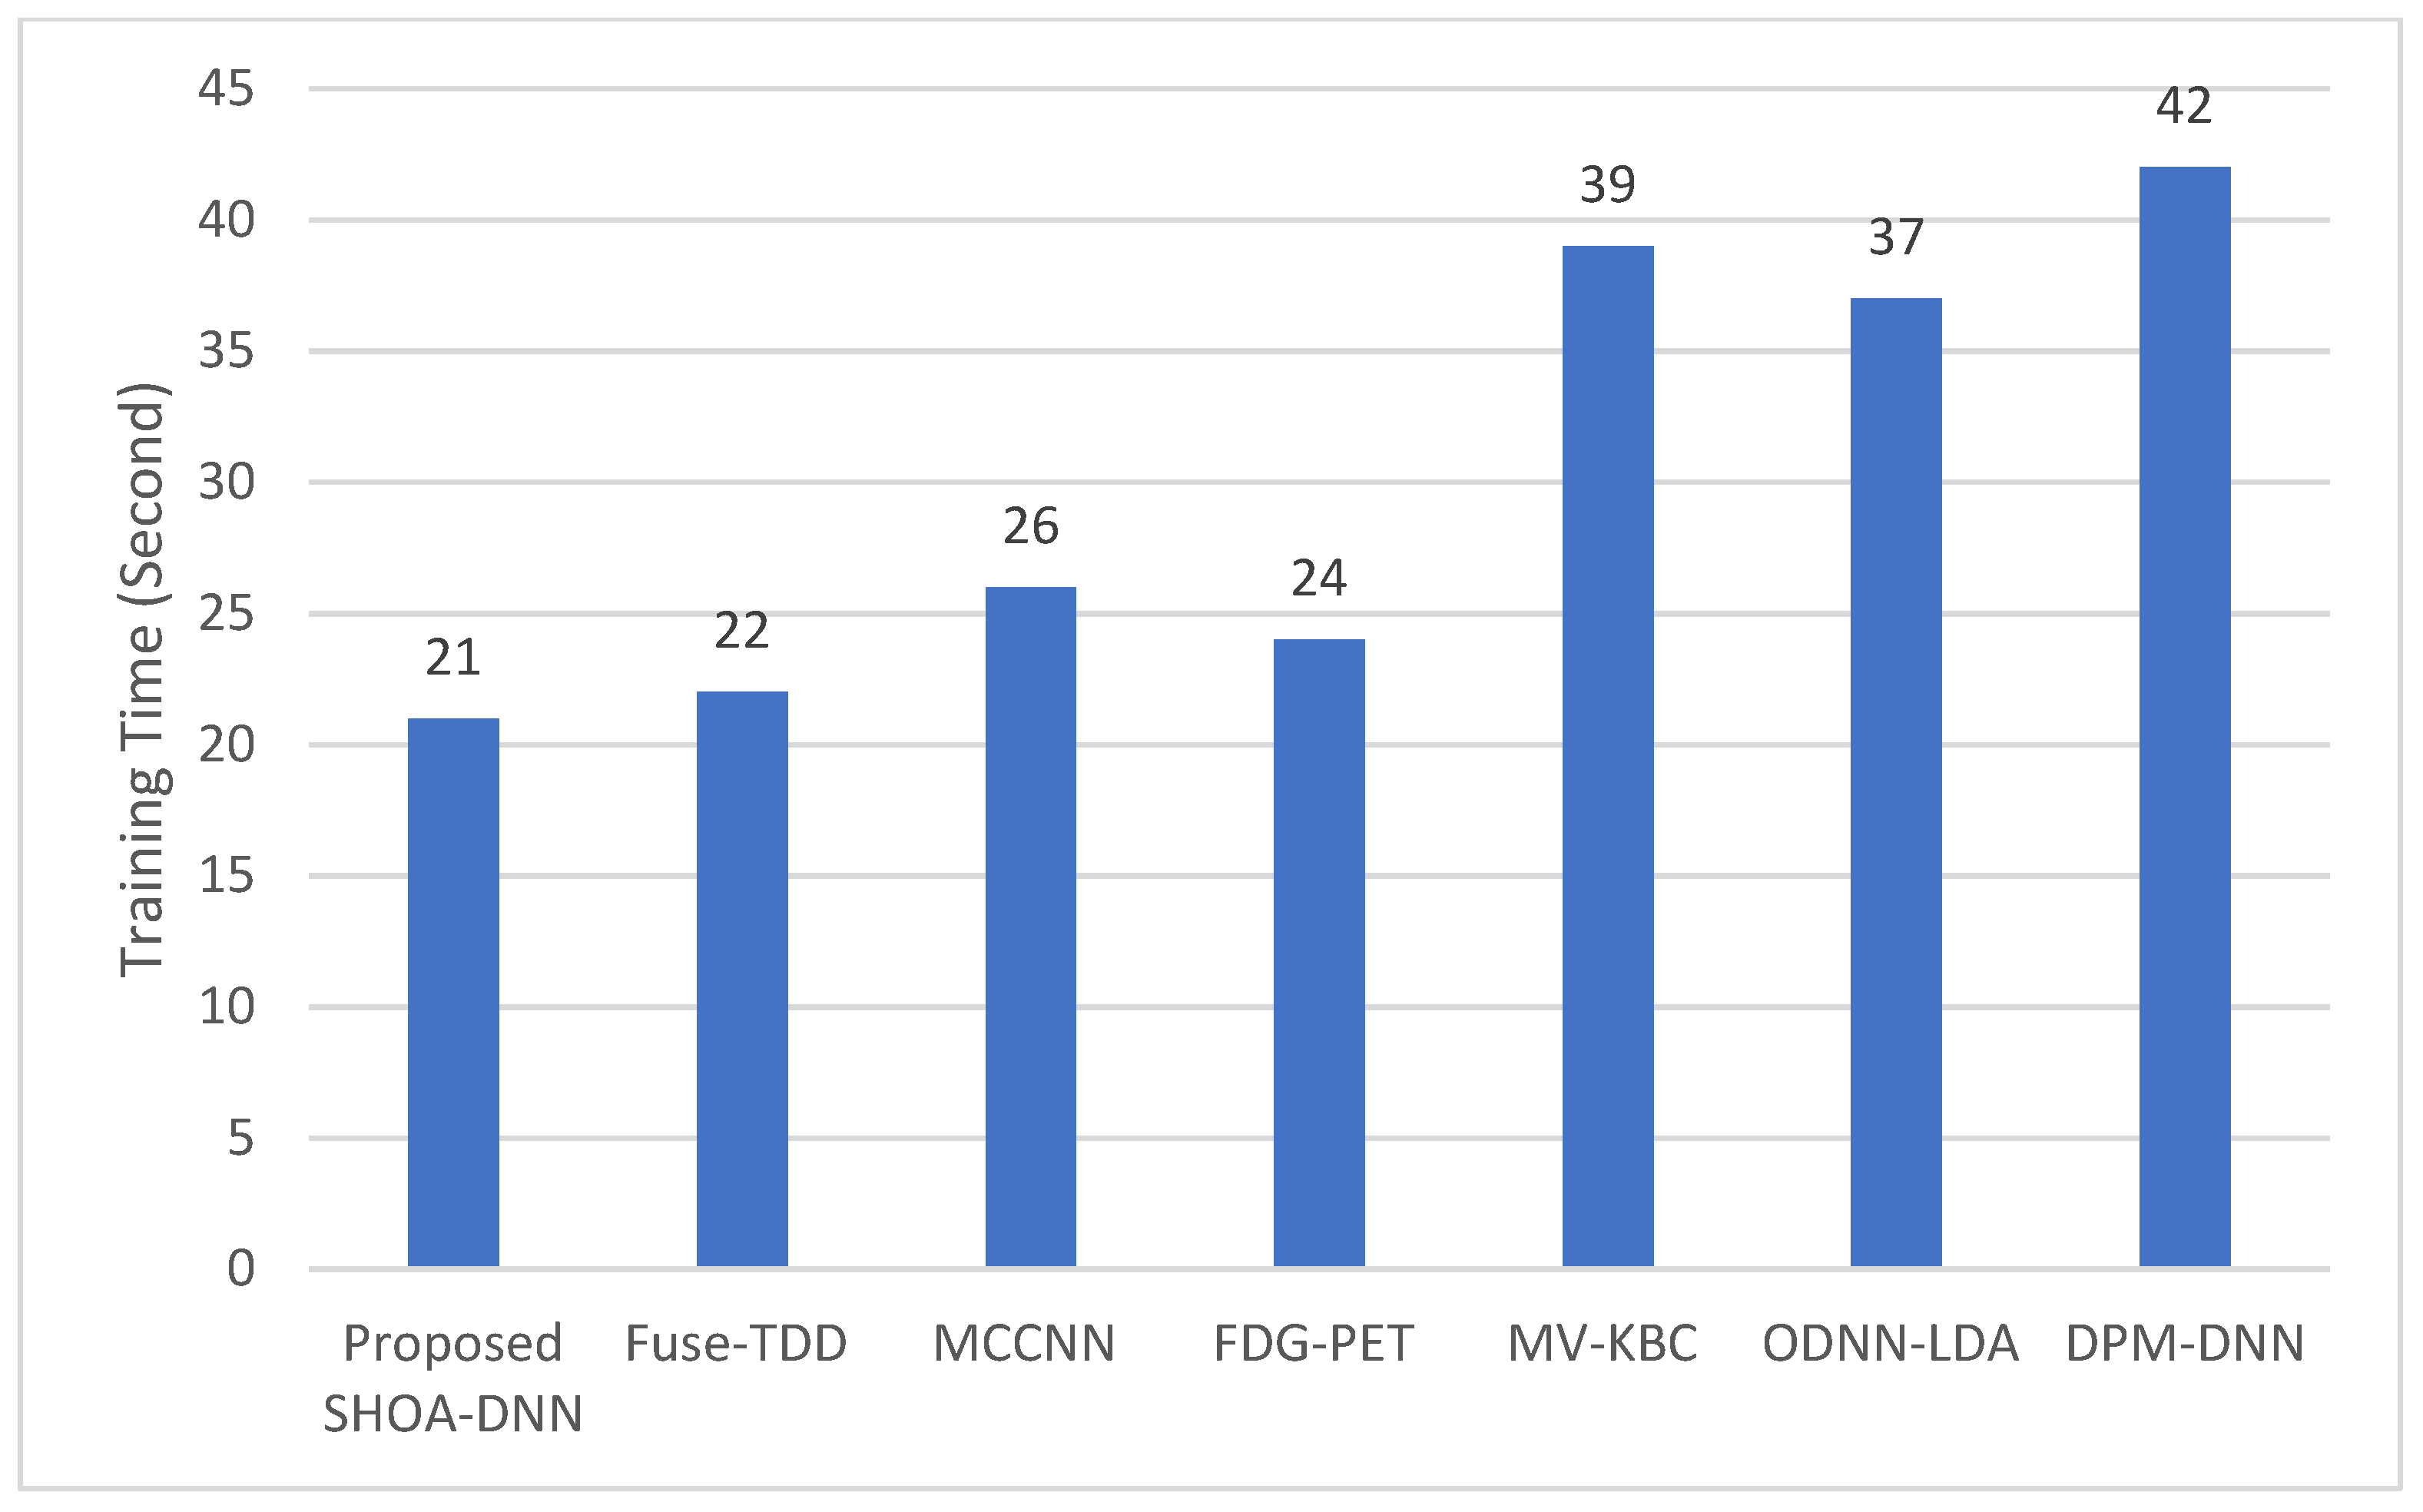

4.3. Performance Evaluation of the Proposed SHOA-DNN Using Training Time and Running Time

| Compared Schemes | Accuracy | Precision | Recall | Specificity | F-Score |

|---|---|---|---|---|---|

| Proposed SHOA-DNN Model | 99.13 | 98.84 | 98.64 | 99.32 | 98.72 |

| Fuse-TDD [18] | 89.53 | - | 84.19 | 92.02 | 89.00 |

| MCCNN [20] | 80.14 | - | 77.00 | 93.00 | 87.00 |

| FDG-PET [22] | 82.60 | - | 92.10 | 53.40 | 82.00 |

| MV-KBC [23] | 91.60 | 87.75 | 86.52 | 94.00 | 87.13 |

| ODNN-LDA [24] | 94.56 | - | 96.2 | 94.2 | 95.12 |

| DPM-DNN [26] | 93.60 | - | - | - | - |